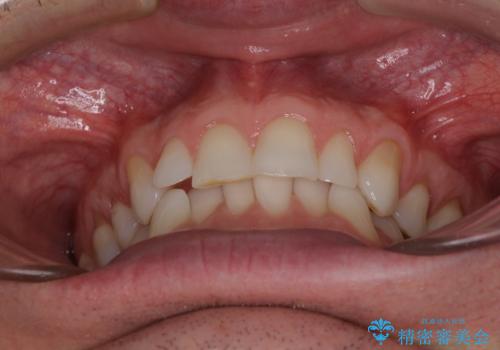

- 上下前歯の叢生を気にして来院された患者様です。

抜歯矯正をした後戻りということで、歯列不正はそれほど大きくなかったため、インビザライン・ライトを用いて矯正治療を行うこととしました。

前歯のデコボコが残っており、シミュレーション通りに動いていない部分がありましたが、再矯正であることやご本人の満足いくところまでデコボコが改善されたとのことで、治療を終了することとしました。